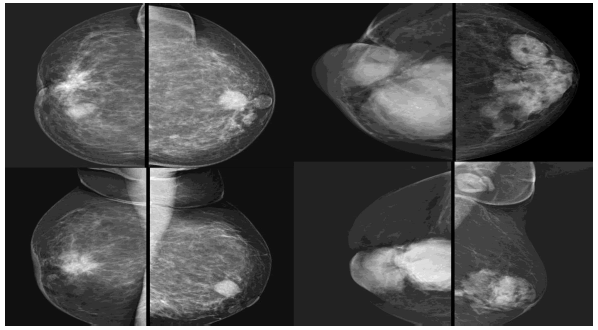

13. Case 16 and 17: Multiple lesions (Figure 18).

Figure 18. Case15: Right breast showing suspicious /probably benign lesion adjacent to the irregular spiculated breast mass lesion (DCC on histopathology) with associated features. The left breast shows a small probably benign lesion in the retro areolar region. Case16: Right breast showing well-circumscribed lesions one overlapping the other (DCC on histopathology) with associated features and left breast showing sclerosing adenosis with significant enlarged left axillary lymph nodes